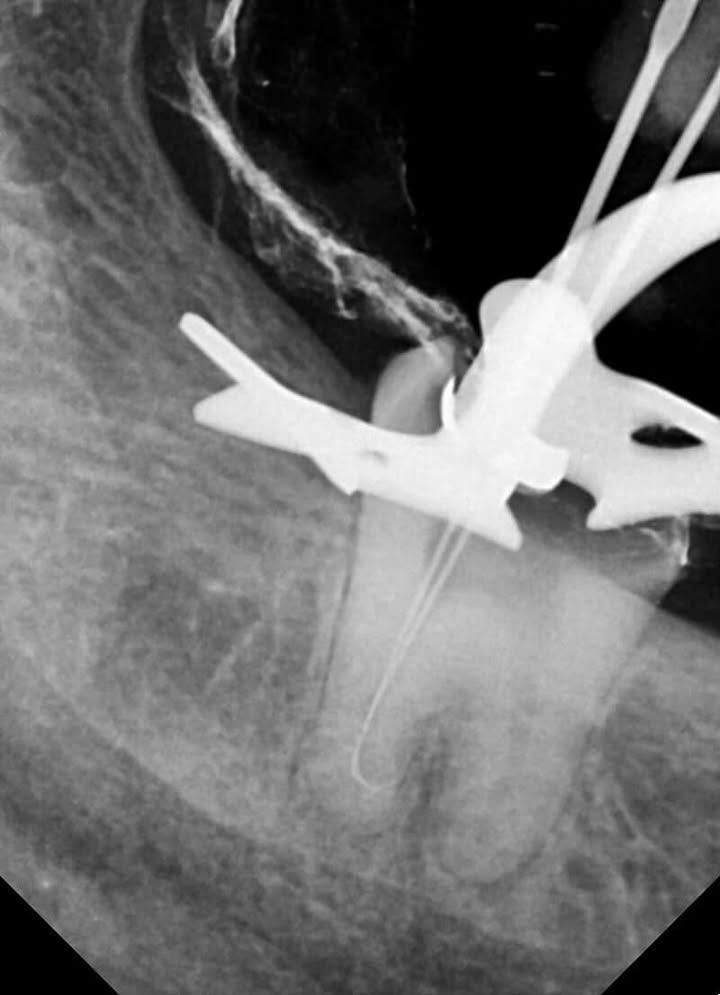

Coronal preflaring was performed using EZ Shaper Pro (EZx) files. - Scouting & Patency Achievement

Manual scouting was carried out with pre-curved hand files up to size 15. When apical blockage was encountered, patency was carefully searched for after appropriate pre-curving of both manual and rotary files. - Final Canal Preparation

- Pre-curve is Key: When apical blockage is encountered without achieving patency, it is essential to carefully search for patency after appropriate pre-curving of both manual and rotary files.